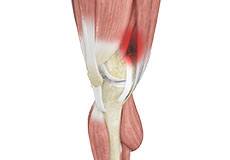

Jumper's Knee

Jumper’s knee, also known as patellar tendinitis, is inflammation of the patellar tendon that connects your kneecap (patella) to your shinbone. This tendon helps in the extension of the lower leg.